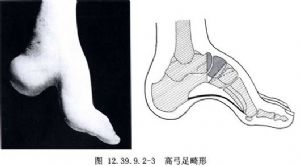

对于跟行高弓足(图12.39.9.2-3),关节融合时应在距下关节处将足向后移位。剥离跖腱膜后,切除楔形骨块以矫正高弓畸形,自距下关节去除楔形骨块以矫正跟骨的旋转。